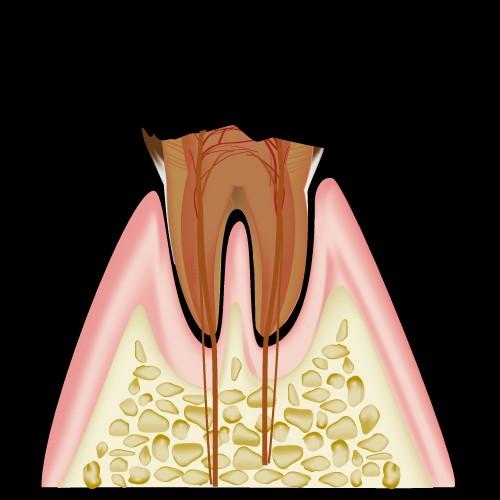

C3:歯髄まで進行した虫歯

C4:歯の根だけが残った状態

この状態を診断することによって

今後どのような治療をするのか

が決定されます。